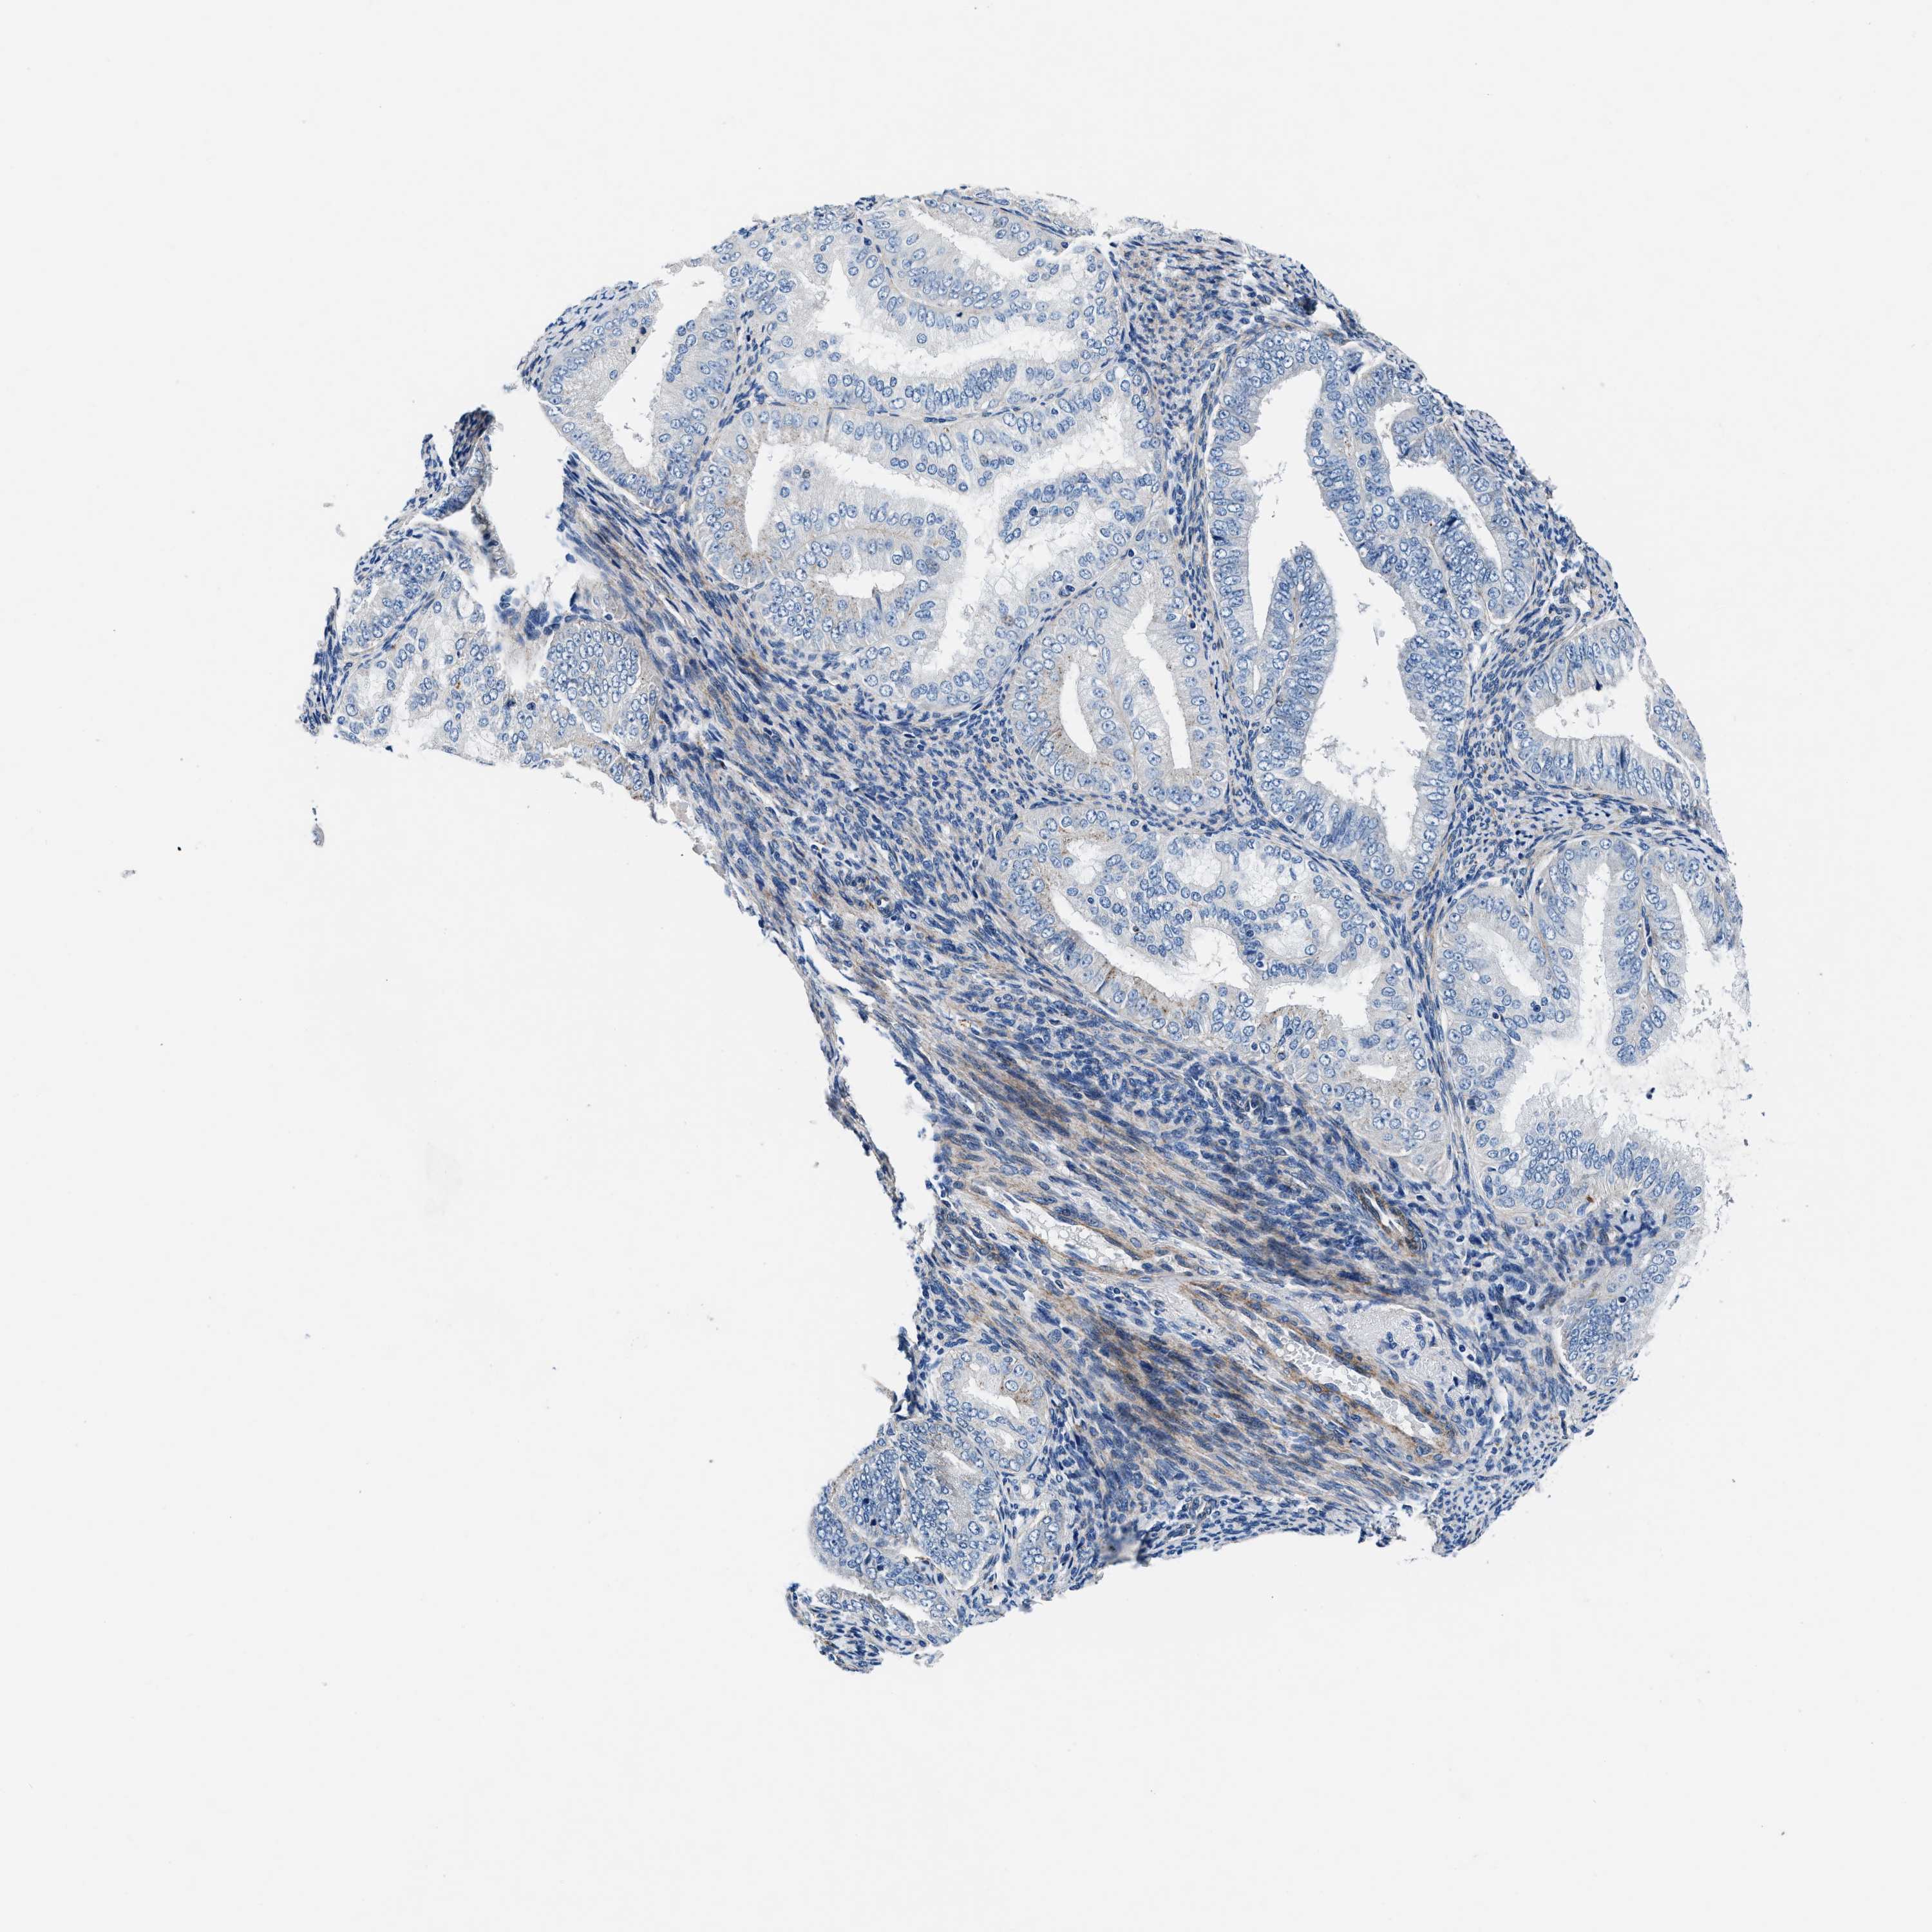

ENDOMETRIAL CANCER - Protein expressioni

A mouse-over function shows sample information and annotation data. Click on an image to view it in a full screen mode. Samples can be filtered based on level of antibody staining by selecting one or several of the following categories: high, medium, low and not detected. The assay and annotation is described here.

Note that samples used for immunohistochemistry by the Human Protein Atlas do not correspond to samples in the TCGA dataset.

Antibody stainingi

Antibody staining in the annotated cell types in the current human tissue is reported as not detected, low, medium, or high, based on conventional immunohistochemistry profiling in selected tissues. This score is based on the combination of the staining intensity and fraction of stained cells.

Each image is clickable and will lead to virtual microscopy that enables deeper exploration of all samples and also displays staining intensity scores, fraction scores and subcellular localization as well as patient and tissue information for each sample.

Antibody CAB001960

Antibody CAB016353

Staining

High

Medium

Low

Not detected

Intensity

Strong

Moderate

Weak

Negative

Quantity

>75%

75%-25%

<25%

None

Location

Nuclear

Cytoplasmic/membranous

Cytoplasmic/membranous,nuclear

Adenocarcinoma, NOS